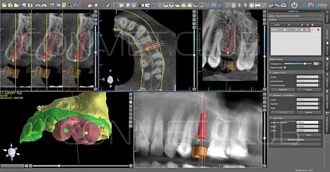

В программе BlueSky Plan были сопоставлены данные КЛКТ и внутриротового сканирования, и проведено планирование операции дентальной имплантации с последующим созданием хирургического направляющего шаблона. Совмещение изображений КТ и внутриротового скананирования позволяет достичь максимальной точности планирования и нивелировать цифровые шумы неизбежно возникающие при КТ исследовании.